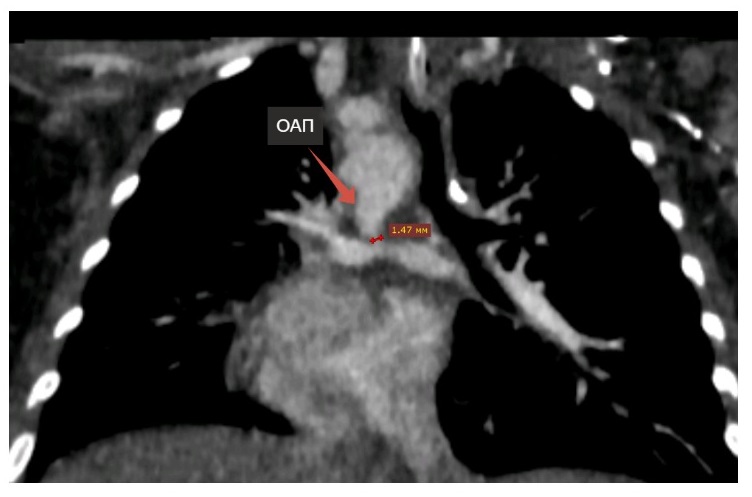

В Таджикистане прооперировать ребенка не смогли, родители проделали большой путь, чтобы дочь смогла получить помощь в Российской Федерации, и обратились к врачам в Иркутске. Девочку с тяжелой гипоксией экстренно госпитализировали и тут же выявили проблему, дополнительно осложнявшую работу легких, - новую коронавирусную инфекцию. Тем временем диаметр открытого артериального протока составлял уже только 1 мм: тоненький сосуд поддерживал жизнь, оставаясь единственным источником легочного кровотока.

Несмотря на острое течение вирусной инфекции у ребенка хирурги Центра Мешалкина по жизненным показаниям провели экстренную паллиативную* эндоваскулярную операцию - через сонную артерию завели катетер внутрь открытого артериального протока и расширили его с помощью стента, обычно используемого для коронарных артерий у взрослых.